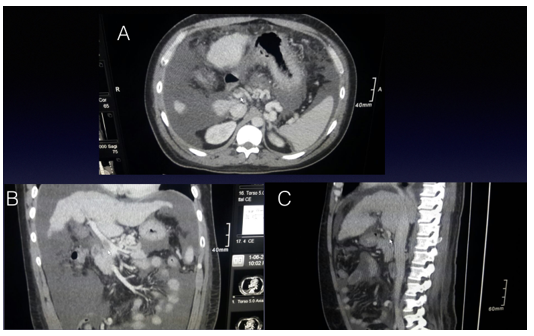

Paciente de sexo masculino de 43 años con enfermedad hepática terminal por hemocromatosis, con un MELD de 30 (MELD, por sus iniciales en inglés Model for End-stage Liver Disease, modelo para la enfermedad hepática terminal). Presenta antecedentes de trombosis de vena porta diagnosticado en el preoperatorio por tomografía computada, en 3 cortes. Figura 1: Trombosis portal grado I (extensión menor al 50%, clasificación de Yerdel y Mc Master)1.

Figura 1: Imágenes de Tomografía Computada, cortes: A-axial, B-coronal y C-sagital de tomografía computada, flecha identifica vena porta con contraste denso con una hipodensidad en su interior que corresponde a trombo.